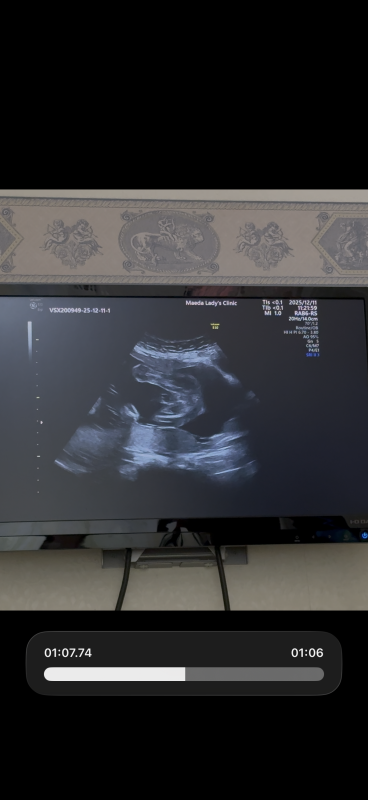

21週になりました!

ですが、まだ性別がわかりません。

いつもエコー見て検索魔になってしまい。

もし分かるのであれば教えて欲しいです

なので断言はできませんが、足と足の間男の子シンボルがはっきりと映っていなそうに感じたのと割れ目が見られるようにも思いましたので、女の子の可能性があるのではと思いました。

しかしはっきりとはわからないため、また次の健診の際に先生へご確認ください。